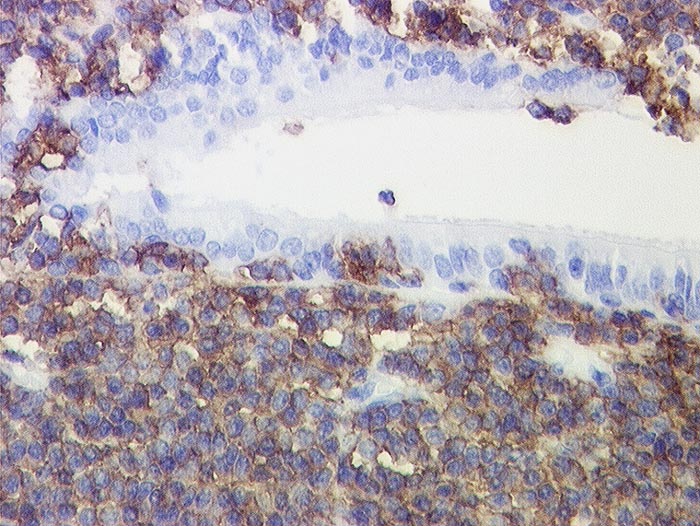

l/ CD20

CD20

Anfärbung:

Zellmembran

Reaktion im Normalgewebe:

Pan B-Zell Marker positiv in allen B Lymphozyten, negativ in Plasmazellen.

Reaktion in Neoplasien:

Die meisten B-Zell Lymphome, etwa 50% der B Zell lymphoblastischen Lymphome und einige Myelome reagieren positiv.

Diagnostischer Nutzen:

Unterscheidung von reaktiven und neoplastischen Infiltraten zusammen mit CD3. Reaktive Infiltrate bestehen meist aus einem Gemisch von B und T Lymphozyten mit Überwiegen der T Lymphozyten. In B-Zell Lymphomen überwiegen CD20 positive B-Zellen.

Unterscheidung von B- und T-Zell Lymphomen.